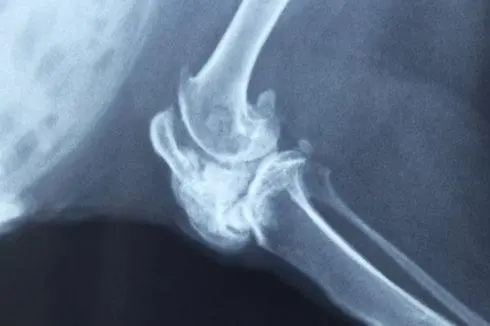

X線所見影像典型,可在組織學(xué)診斷之前作出診斷。

基本影像是密度增高不透X線的影像,是由于腫瘤內(nèi)軟骨的鈣化、骨化所引起。與中心性軟骨肉瘤相比,周圍性軟骨肉瘤的鈣化更常見且更廣泛,在許多病例中,這種密度增高的影像幾乎遍布整個(gè)腫物。因此,在周圍性軟骨肉瘤中,可看到一骨外腫物,呈模糊分葉狀,表面凹凸不平像花椰菜樣,密度很高。在腫瘤較厚的區(qū)域不引起象牙狀的高密度影像,可以看到鈣化無一定的結(jié)構(gòu),呈典型的結(jié)節(jié)狀、點(diǎn)狀和環(huán)形(相應(yīng)于軟骨樣的分葉和周邊形成)。腫物表面的鈣化較少,至使腫瘤與軟組織的界限模糊。

在很少見的極早期病例中,周圍性軟骨肉瘤在影像上仍表現(xiàn)為骨軟骨瘤的影像,其惡性演變可通過CT、MRI、大體病理和組織病理而確定,其骨掃描不是在成人期應(yīng)當(dāng)?shù)年幮?,而是?qiáng)陽性。

1、骨軟骨瘤的不透X線影像的密度高、不規(guī)則,與軟組織有明顯的邊界;相反,周圍性軟骨肉瘤的部分區(qū)域與軟組織的界限不清,CT、MRI有助于發(fā)現(xiàn)周圍性軟骨肉瘤的軟骨帽變厚,并可與骨軟骨瘤的頂部的積液相鑒別,骨掃描在成人期的骨軟骨瘤中為弱陽性,在周圍性軟骨肉瘤中為強(qiáng)陽性,此外,腫瘤在成人期繼續(xù)生長也支持周圍性軟骨肉瘤的診斷,可連續(xù)攝X線片觀察。